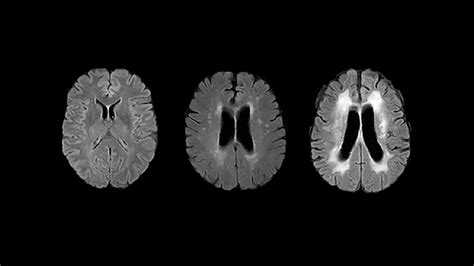

• Atrophy: The brain tissue volume is appropriate for your age group, showing no unexpected shrinkage.

• Ischemic Changes: No evidence of past strokes or restricted blood flow.

• Edema: No signs of abnormal fluid buildup or brain swelling.

Feature Evaluated Characteristics of a Normal Brain MRI Potential Areas of Concern

Brain Tissue Symmetrical, distinct gray/white matter Asymmetry, lesions, or signal changes

Ventricles Normal size, no midline shift Enlarged, compressed, or shifted

Signal Intensity Uniform and consistent Hyperintensities or "spots" (gliosis)